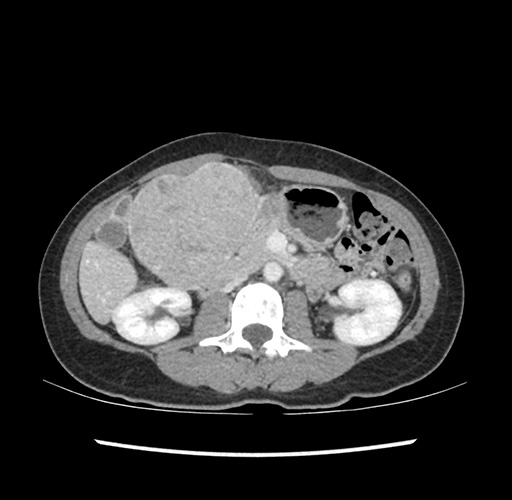

Imaging Analysis

Look through the patient's CT scan to identify any areas of concern for the necessary procedure.

Based on your CT findings, which issue(s) would give reason for "planned slowing down moment(s)" in this case?

Considering a standard left lateral sectionectomy procedure, what step(s) of the operation would you do differently in this case ?